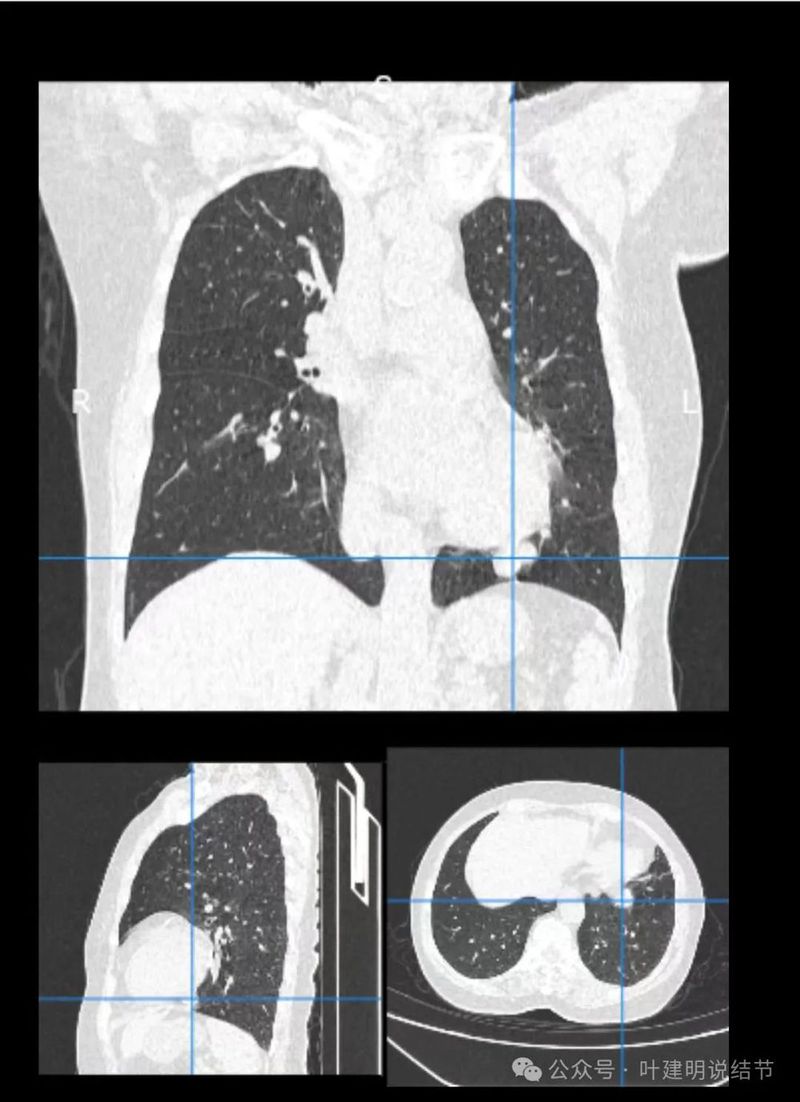

冠状位见病灶与周围结构有间隙,说明不像炎性,如果是炎症,挨这么近,一般会搭牢的。

矢状位病灶膨胀感不如横断们与冠状位明显,但东西是实性的。

轴位病灶实性,分叶,膨胀!

病灶表面不平,有浅分叶,与膈肌之间有间隙。

与膈肌之间间隙明显,病灶实性,膨胀性明显,边缘相对较为光滑。

病灶浅分叶,膨胀性,周围有很淡的磨玻璃密度似的,这可能是检查时屏气屏得不太好的关系,不太符合混合磨玻璃结节的样子。

整体感觉较圆,膨胀性是明显的。膈肌有点被它顶过去的样子。